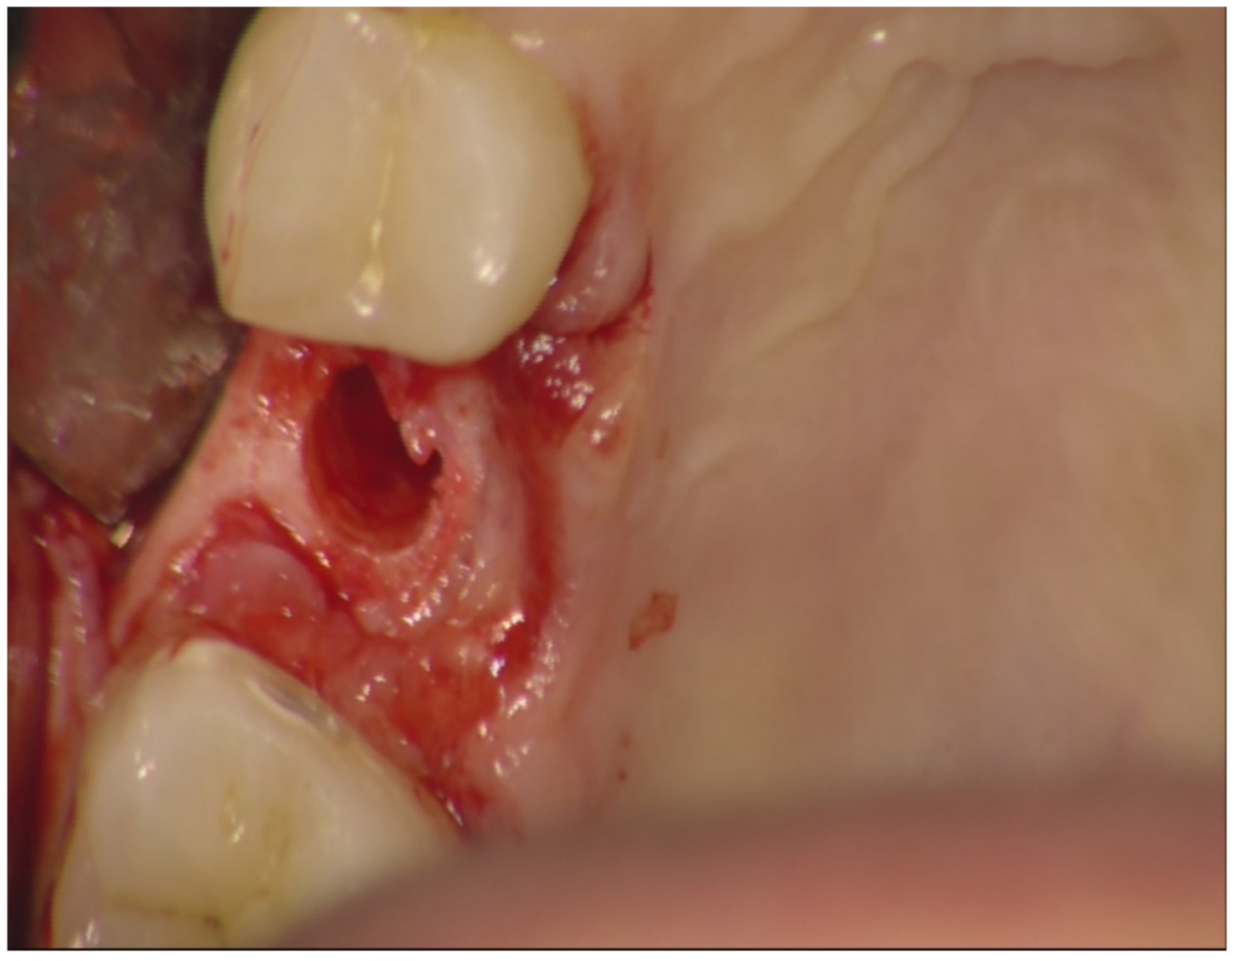

Before surgery, all patients underwent professional oral hygiene with periodontal treatment and supportive therapy, if needed. At the end of the prevention phase, the patients were moved to a careful home and professional oral-hygiene maintenance. Radiographic examination, including periapical radiographs (Figure 1), and computer tomography or CBCT scans, were also performed. All the implants were placed according to a predefined protocol, which includes antibiotic prophylaxis with amoxicillin clavulanate 1 gr every 12 h for six days, starting from the day of the surgery, following by a rinse with 0.2% chlorhexidine (CHX) solution for 1 min. Local anesthesia was performed with a 4% solution of articaine with epinephrine 1:100,000. All the implants were inserted after crestal and intrasulcular incisions performed to raise a mucoperiosteal flap. All the implants were 4.3 mm of diameter (Nobel Replace CC PMC Tapered, Nobel Biocare, Zurich, Switzerland), with 0.75 mm of machined collar. The implant sites were prepared using the lance drill of 1.5 mm of diameter to sign the implant position. Then the twist drill of 2 mm of diameter was used to reach the sinus floor cortex with a drill stop positioned 0.5 mm below the maxillary sinus floor (working length), estimated by using the CT or CBCT scan. Finally, the narrow platform drill (made for 3.5 mm diameter implants, Figure 2) was used at the working length to underprepare the implant recipient site. A collagen matrix (Condress, Smith and Nephew, Agrate Brianza, Italy) was inserted in the prepared site and then the sinus floor was fractured with a calibrated osteotome of 3.5 mm of diameter (Nobel Biocare). At this point, graft material consisting of 0.5 g. of deproteinized anorganic bovine bone, in small microgranules of 0.25–1 mm (Bio-Oss, Geistlich Pharma, Switzerland), mixed with sterile saline, was compacted into the sinus using the same osteotome, up to the working length (Figure 3). At the end of this procedure, all the implants were inserted according to a one-stage protocol [28,29], reaching a primary implant stability from 30 to 50 Ncm. All the implants were 8 to 10 mm of length (Figure 4), depending of the residual bone height. After implant placement, all the patients received oral and written recommendations about the correct maintenance, oral hygiene (i.e., mouthwash 0.2 CHX solutions twice a day, no brushing implant areas), and soft diet. Patients were also instructed to avoid any increase of the intrasinus pressure. The postoperative analgesic treatment was performed with ibuprofen 600 mg, as needed, but a maximum every eight hours for two to three days after the intervention. About two weeks after surgery, sutures were removed.

Figure 1.

Preoperative periapical X-ray.